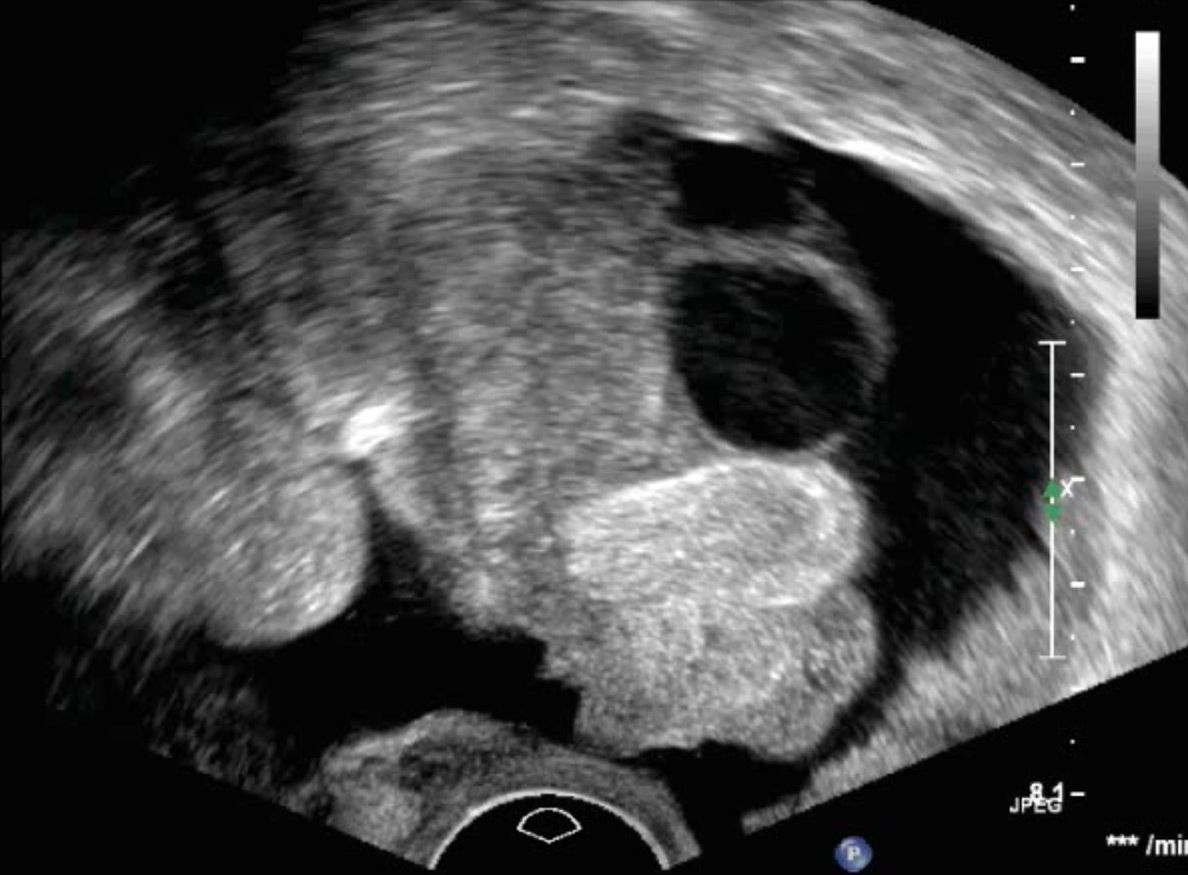

Dermoidzyste

Ovarialkarzinom

Veränderungen des Eierstocks sind gerade vor den Wechseljahren häufig funktioneller Natur und durch zyklusbedingte Einflüsse zu erklären. Diese sollten nicht beunruhigen und sind in aller Regel im natürlichen Verlauf abzuwarten. Raumforderungen am Eierstock können aber auch Beschwerden hervorrufen. Zum anderen sollten sie gegen bösartige Veränderungen abgegrenzt werden. Letztere sind selten, jedoch von ungünstiger Prognose, wenn sie ein fortgeschrittenes Stadium erreicht haben.

Die Abgrenzung zwischen einer einfachen funktionellen Veränderung, einer gutartigen Veränderung oder einer potentiell bösartigen Veränderung sollte primär sonographisch erfolgen.

In erfahrener Hand kann hier der Verdacht entweder bereits ausgeräumt werden oder eine operative Abklärung in gemeinsamer Planung mit den hiesigen Operateuren eingeleitet werden. Die korrekte Erkennung von bösartigen Befunden des Eierstocks gelingt in erfahrener Hand in über

98% der Fälle.